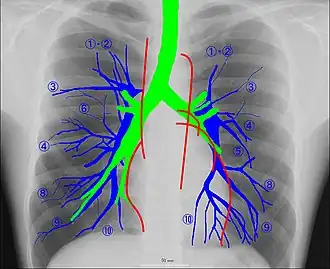

Рентгеноанатомия органов грудной клетки.

Рентгеноанатомия органов грудной клетки. Зелёным обозначены трахея и крупные бронхи, синим — ветви лёгочных артерий, красным — дуги тени сердца, цифрами отмечены сегменты лёгких.

При изучении рентгеноанатомии органов грудной клетки обращают внимание на рентгеновскую структуру видимых костей и мягких тканей грудной клетки; форму и прозрачность для рентгеновских лучей областей, на которые проецируется лёгочная ткань (так называемых «лёгочных полей»), а также их структуру, сформированную тенями сосудов лёгких («лёгочный рисунок»); расположение и структурность корней лёгких; положение, форму куполов диафрагмы и синусов плевральных полостей; форму и размеры тени средостения (в том числе сердца).

Лёгкие на рентгенограмме образуют лёгочные поля, располагающиеся по обе стороны от интенсивной тени средостения. Правое лёгочное поле короче и шире левого. В лёгочных полях различают верхушки (зоны выше ключиц), верхние отделы — от верхушек до передних отрезков вторых рёбер, средние отделы — между вторыми и четвёртыми парами рёбер, и нижние отделы — от четвёртых рёбер до диафрагмы. Лёгочные поля в норме очень светлые (тёмные на негативе) из-за высокой рентгенопроницаемости заполненной воздухом лёгочной ткани. Структура лёгочных полей называется лёгочным рисунком, анатомическим субстратом которого являются лёгочные сосуды и, в малой степени, лёгочный интерстиций. Лёгочный рисунок визуализируется в виде переплетения сосудистых теней тяжистого, округлого и овального вида, более интенсивных в местах их пересечений. В направлении от корней лёгких к периферии рисунок лёгочных сосудов становится беднее и совсем не визуализируется на расстоянии 1—1,5 см от края лёгочных полей. Лёгочный рисунок наиболее густой в нижних отделах лёгочных полей, обедняясь к верхушкам. Тени бронхов на рентгенограмме визуализируется в виде двойных полосок или колец с просветлением внутри.[3][4]

Тень корней лёгких определяется парамедиастинально на уровне передних отрезков II—IV рёбер, левый корень располагается несколько выше правого и частично скрыт тенью средостения. Ведущим анатомическим субстратом в формировании тени корней лёгких являются лёгочные артерии и бронхи, в меньшей степени — лёгочные вены и другие структуры. В норме корни лёгких имеют неоднородное изображение, представляя собой структурированную совокупность элементов различной плотности. В корнях лёгких различают головку, тело и хвост. Правый корень визуализируется на всём протяжении в виде лентовидной, суживающейся книзу изогнутой тени средней интенсивности, отделённой от тени сердца промежуточным и нижнедолевым бронхами. К периферии от корней лёгких отходят лёгочные сосуды, причём артериальные ветви имеют более вертикальное направление, венозные — более горизонтальное. Ширина корня лёгкого соответствует ширине его основного артериального ствола; в норме она равна ширине бронха, отделяющего корень от средостения, и не превышает 1,5 см.[3][4]